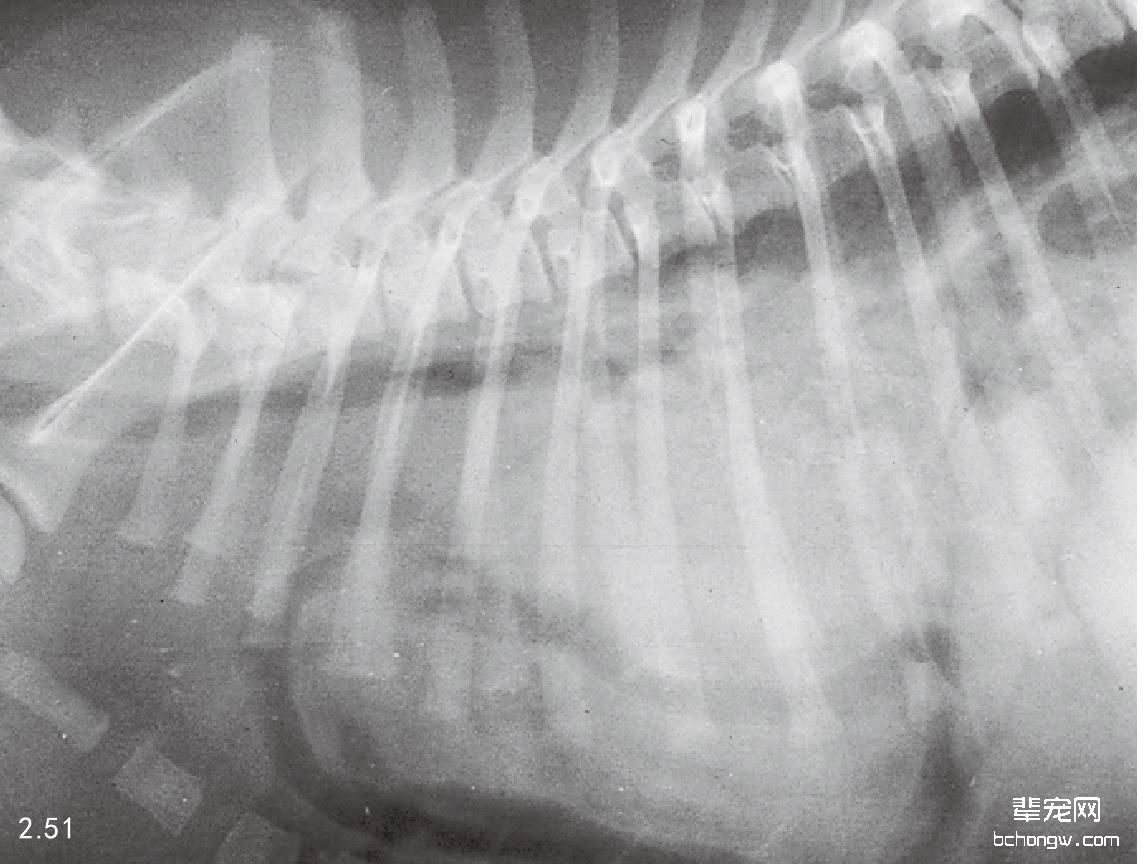

X线检查 最常见的X线影像是横膈膜线消失、正常的胸腔内解剖构造消失,肺叶、心脏和胸腔纵隔伴发移 位(图2.51)。胸腔内有腹腔脏器存在同样腹腔内脏器移位或缺失。胸膜渗出可能存在,特别是肝脏或脾脏钳闭 在横膈膜破裂口中时。如果平片影像不清,钡餐检查有助于确定腹腔器官的位置。在先天性横膈膜疝中,脏器 可能被包含在心包囊中,呈现一个独立的胸腔肿块与横膈膜相连(图2.52)。

图2.51 横膈膜破裂的3岁可卡犬的侧面胸腔X线片:横膈膜左侧破裂,并可见肠管进入胸腔。